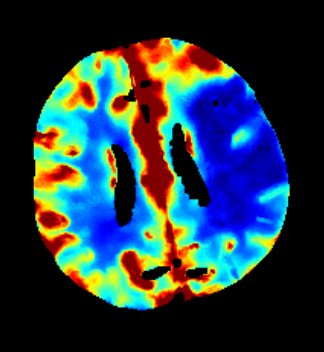

Des Weiteren ist mRay in der Lage eine Verarbeitung von Bildern durchzuführen und so Veränderungen bzw. Anomalien in Geweben zu finden, zu visualisieren und zu quantifizieren. Das Bildverarbeitungsmodul mRay VEOcore kann verwendet werden, um Bilder des Gehirns von Bildgebungsmodalitäten wie CT, Perfusions-CT oder MRT mit diffusionsgewichteter Auswertung (DWI) zu prozessieren. Als Ergebnis werden Kontrastveränderungen über die Zeit als farbige Perfusionskarten angezeigt, dies beinhaltet auch flussbasierte Parameter und Gewebeblutvolumen Berechnungen.

Die Perfusionsanalyse von Aufnahmen des Gehirns ermöglicht die Darstellung und Quantifizierung von minderdurchblutetem Gewebe (Penumbra), nicht-durchblutetem Gewebe (Kerngewebe) und dem Mismatch-Ratio zwischen den beiden Werten. Die berechneten Werte können der Unterstützung bei einer Entscheidungsfindung dienen, die auf der Beurteilung des Ausmaßes der Schädigung von Geweben basiert.